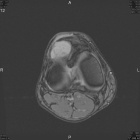

Patient is a 45 y/o Ortho nurse who presented w/ enlarging painful R. knee mass for past year; PMH: ovarian cysts s/p rupture

PE: R. knee w/ well circumscribed mass at the lat. aspect of the patella; + tenderness to palpation; normal PROM; NVI

Zoom image: Radiological image Radiological image.